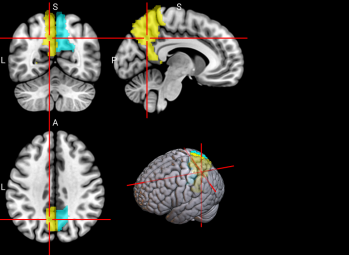

128

R Ventral Lateral nucleus of the thalamus (tAV)

The ventral lateral nucleus of the thalamus plays an important role in motor control and receiving, integrating, and projecting inputs from cerebellum, striatum, and cortex to the primary motor cortex [68].

/word/media/image17.png/word/media/image17.png